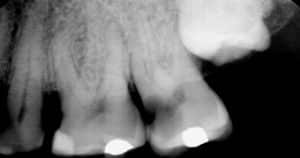

Wenn Bakterien durch eine tiefe Karies, eine alte Füllung oder einen Riss in den Zahn gelangen, entzündet sich der Nerv.